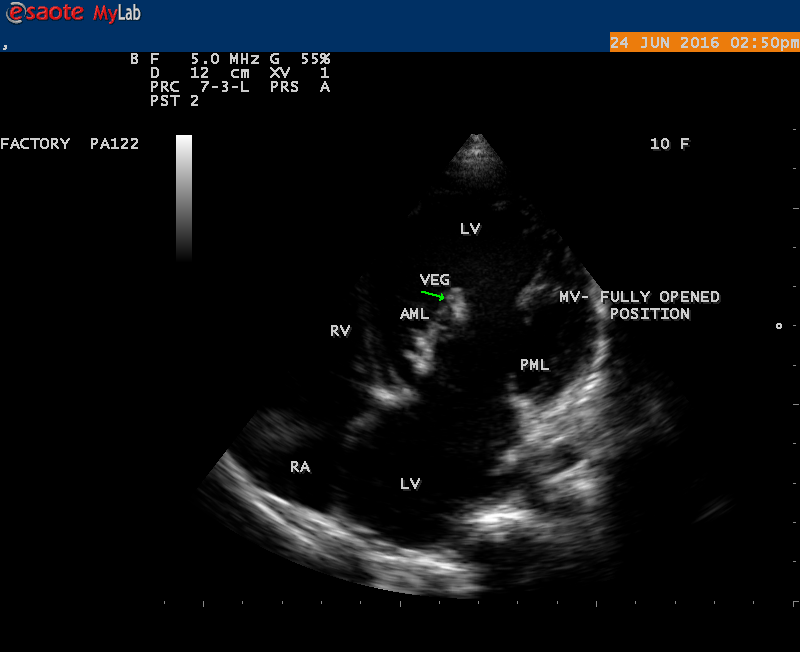

The most common and direct evidence of infective endocarditis is the vegetation and it begins as a microscopic focus of infection and gradually grows into a conspicuous mass. It is typically an irregularly shaped, highly mobile, echogenic mass attached to the free edge of a valve leaflet ( most commonly at the coaptation line) and tends to develop on the ‘upstream’ side of the valve leaflets ( ie, the ventricular side of aortic valve and the atrial side of mitral and tricuspid valves. They may be seesile or pedunculated, but usually has an oscillating or fluttering motion, a typical feature of most vegetations. Vegetation move with the leaflet in a more chaotic (‘oscillating’) manner and it may prolapse through the valve into the LV (left ventricle) as it opens as shown in Figures 3, 4 and 16 and into LA (left atrium) as it closing (Figure 5 and 6) . The mass of vegetation is typically homogeneous with echogenicity similar to that of the myocardium. The infectious process often alter the valvular structure and function. Extensive involvement of the leaflet may result in chordal rupture, leading to severe regurgitation as shown in Figure 21 . Direct and typical signs of RMCT (ruptured mitral chordate tendineae) were chain-flail or whiplash-like changes and had an incidence of 86.7%, causing severe regurgitation and mitral chordal rupture is the leading cause of flail mitral leaflet[30]. A large vegetation may obstruct the valve orifice as shown in Figure 1 and 2 , sometimes termed as “obstructive-type bacterial endocarditis” and producing a functional valve stenosis ( Ping-Pong mitral stenosis [31]) similar to left atrial myxoma as shown in Figure 29.

The size and shape of vegetation vary due to curling of vegetation. The size of vegetation in this child is 35.6 x 9.3 mm as in Figure 17 , 20 x 23.7 mm as in Figure 1 , 32.9 x 13.9 mm as in Figure 2 .

The shape of vegetation varies in this child as ‘popcorn’ like (Figures 1,3 and 4 ), rod-shaped (Figure ), basket shaped (Figure 7 )[33-Figure 13.3], ‘baby in hand’ appearance (Figure 18), ‘cucumber shaped (Figure 2 ) and a ‘bunch of plantain’appearance (Figure 33 ), ring shaped (Figure 19 }, bileaflet structure (Figure 9 )with bileaflet MR jet as shown in Figure 10 . and kissing forms (Figure 13 - parasternal long axis view, Figure 14 - apical four chamber view and Figure 15 - short axis view)